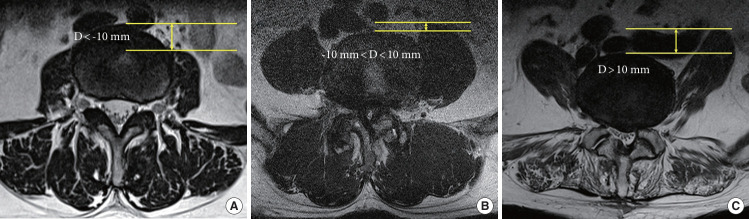

Methods: This retrospective study examined a cohort of 465 patients who underwent OLIF from 2015 to 2023. Patient demographics, comorbidities, pre- and postoperative laboratory test results, and perioperative status were assessed. General condition of patients was assessed using the modified frailty index-11 (mFI-11), prognostic nutrition index, and geriatric nutrition risk index. In OLIF, the size and location of the psoas muscle involved in retraction and its relationship with the vertebral body were also investigated.

Results: POI occurred in 19 patients (4%). Lower mFI-11 was linked to a higher risk of POI. While psoas muscle size had no significant effect on the risk of POI, the anterior location of the psoas muscle relative to the vertebral body was associated with a higher occurrence of POI. Multivariate logistic regression analysis of POI identified mFI-11 as the most significant risk factor (p = 0.003).